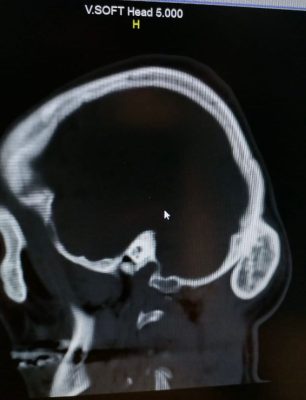

وقال الفريق الطبي بانه فور وصول المريض أجريت له كامل الفحوصات المخبرية والمقطعية على المخ واشعة ثلاثية الابعاد حيث تبين وجود ورم حميد في القشرة الخارجية من عظام الجمجمة.